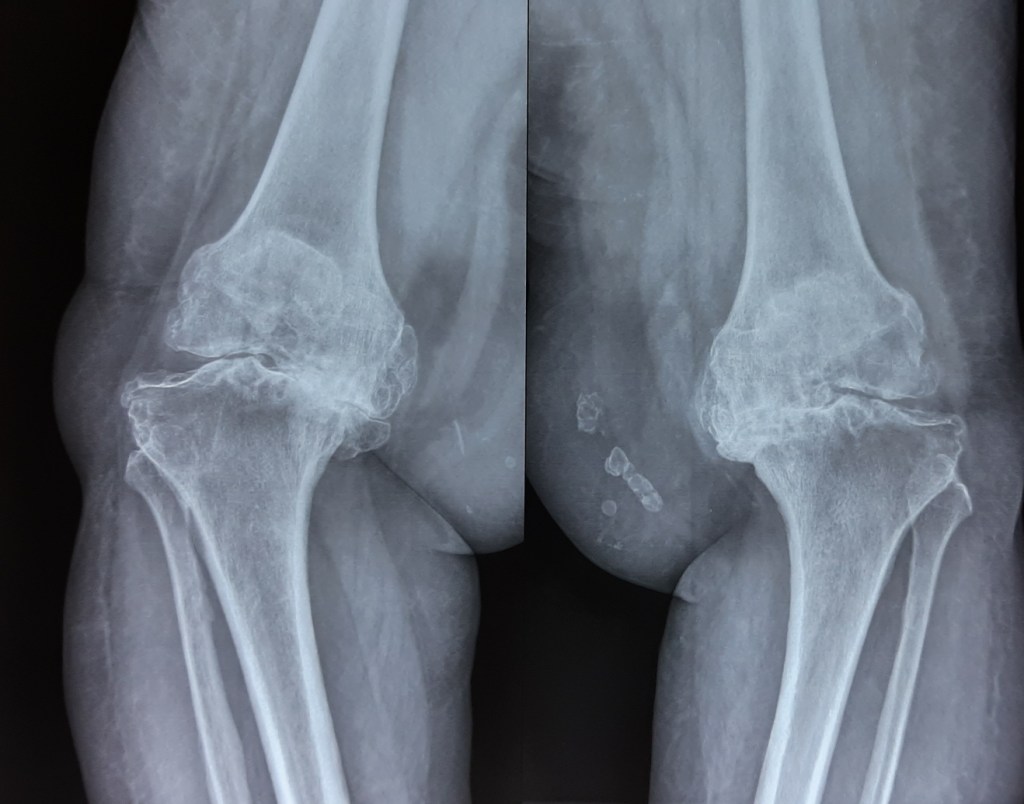

Total Knee Replacement is one of the most commonly performed orthopedic surgery. It involves replacing the articular surfaces (femoral condyles and tibial plateau) of the knee joint with smooth metal and highly cross-linked polyethylene plastic. It helps to relieve pain and restore function in severely diseased knee joints.